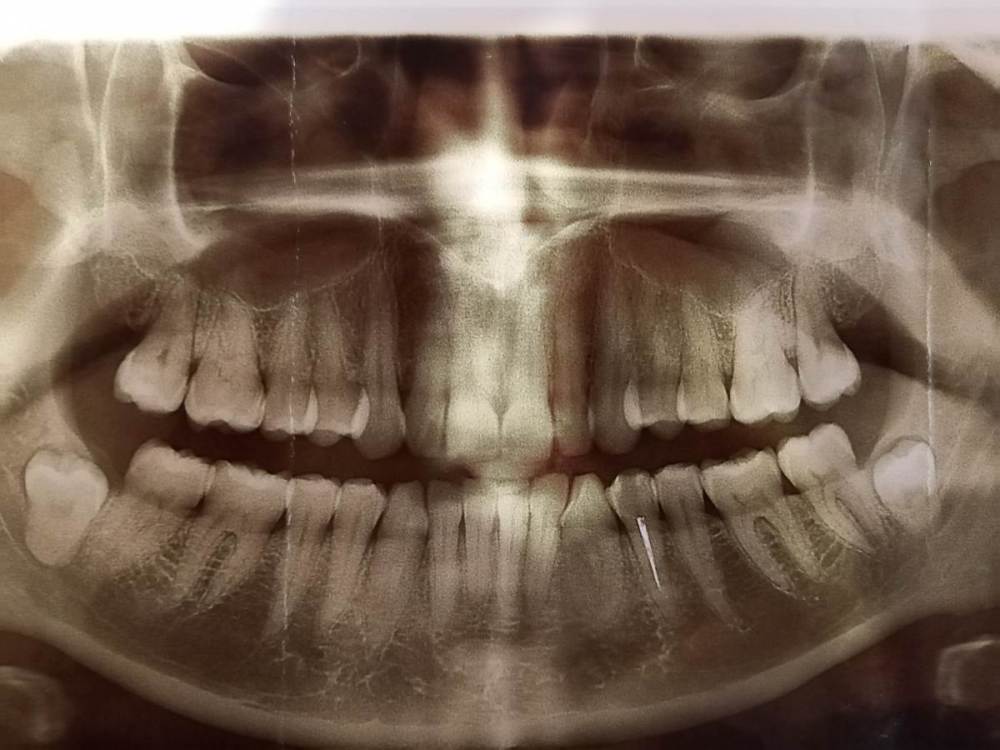

СмирноваД Опубликовано 21 июня, 2022 Поделиться Опубликовано 21 июня, 2022 Здравствуйте Уважаемые стоматологи! Много расписывать не буду, т.к. Долго это. Посмотрите пожалуйста снимок. (также имеется Кт) т.к болит Вся правая сторона головы, и нерв стреляет , то в какой-нибудь верхний зуб, то бывает в нижний какой-нибудь. ТО в язык бывает. Постоянные колики. И отдает по всей стороне головы. От куда это все идет просто не возможно понять. Все это дерганье и напряжение постоянно(щека, верхние зубы, нижние зубы, язык, нос, ухо, висок.).Усиливается к вечеру, но с утра затихает и нарастает в течении полу часа. Стоматологи отправляют к неврологам. Неврологи и стоматоневролог, невралгию отрицают. ЧЛХ тоже особо ни чего страшного не видят. Единственное что видят, это лечить ВНЧС. 1.В июне 2021 года удалили ретинированный 48 зуб. Но боли так и не проходят. Постоянно дергает щеку. Больно глотать слюну и разговаривать. На КТ несколько врачей заметили осколок, но не гарантируют, что после удаления боли пройдут. 2. Имеется еще зуб 1.7. в 2019г. запломбирована коронка и сбоку со стороны щеки тоже пломба прям под десну уходит. Но его не лечили. И он начинает чернеть вокруг пломбы. 3.Так же болит в районе зубов 1.1. и 1.2 при разговоре больно касаться десны и при нажатии возле носа не приятно. Там же пульсирует, нерв стреляет , усиливается при наклоне головы, при физической работе, разговоре. И отдает в нос.. Стоматологи сказали чистить, т.к. много камней было, но это не помогло. 4. И напряжение в 4.1 и 4.2. как буд-то отдает от куда-то. Ссылка на комментарий

СмирноваД Опубликовано 21 июня, 2022 Автор Поделиться Опубликовано 21 июня, 2022 Сказать трудно. С 2019 года по врачам бегаю. Тут одно на другое накладывается. До удаления зуба 4.8 было просто кошмар, эти боли были раз в 20 сильне. После удаления 7ка восстанавливалась пол года и в это время болел 3.8. От напряжения Был такой сильный спазм мышц, что нижними зубами била по верхним зубам, думала сломаю и в один прекрасный день сильно заныл 1.1, а потом почернел, как мне кажется, что треснула эмаль, т.к после чистки он побелел, но а потом опять сразу окрасился. Ссылка на комментарий

СмирноваД Опубликовано 23 марта, 2023 Автор Поделиться Опубликовано 23 марта, 2023 В общем, вскрыл мне зуб 1.2.с периодонтитом. Сделали шину,но как болела вся правая сторона, так и болит. Вечно нерв бьёт, разговаривать и глотать больно, как будто вся сторона воспалена. От шины немного легче. Ещё на КТ видно под 4. 6 зубом какое-то образование, но толком внятного ответа, что это такое, я не услышала. Уважаемые врачи, ответьте пожалуйста на пару вопросов:1.что это такое за белое на снимке и какие последствия от него могут быть. 2.И что думаете про смещение суставного диска кнаружи 5мм(заключение по мрт внчс)?Зарание Спасибо за уделённое время. Ссылка на комментарий